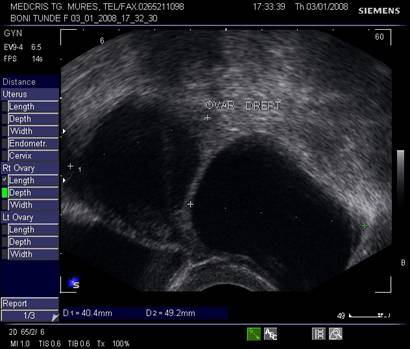

Fig. nr.395.Plex venos dilatat , parametral ( diagnostic diferential cu un chist ovarian, dificil uneori , la ecografia transvaginala )